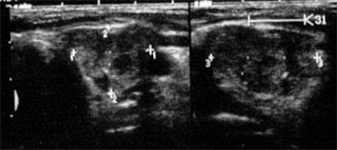

Die Sonographie mit hoch auflösenden Schallköpfen (7,5 bis 12,5 MHz mit Duplex) stellt heute bereits wenige Millimeter große Herdbefune präzise dar. Es existieren sonographische Kriterien, auf deren Basis, maligne Schilddrüsenknoten mit sehr hoher Sicherheit identifiziert werden können. Hierzu gehören unter anderem die Hypoechogenität, die unregelmäßige Randbegrenzung, Mikroverkalkungen sowie eine zentral verstärkte Vaskularisation.